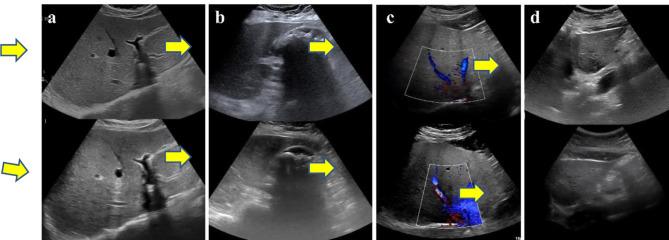

To investigate the feasibility of robot-assisted teleultrasound diagnosis for radioactive patients compared with conventional ultrasound diagnosis. In this prospective study (ChineseClinicalTrials.gov identifier, ChiCTR2200057253), 32 radioactive patients were examined by conventional ultrasound and MGIUS-R3 robot-assisted ultrasound from March 2022 to June 2022. After two scans, patients completed a satisfaction survey, including comfort score, fear score, tension score and pain score. The durations of both scans were recorded, and sonographers wore lead apron to prevent the radiation during the conventional examination. Subsequently, the ultrasonic images saved by sonographers were diagnosed and scored. Finally, we evaluated the feasibility of the robot-assisted teleultrasound diagnosis system regarding patients' satisfaction, examination duration, image quality and diagnostic consistency via χ test, Kappa consistency test and Wilcoxon signed-rank test. Among 32 patients (mean age, 54.9 ± 9.8 [SD]; 16 women), 29 had consistent diagnoses and 3 had inconsistent diagnoses between two scans, but the diagnostic consistency was good (Kappa = 0.818, P < 0.001). In addition, there was no statistical difference between two scans with regard to image quality score (29.28 ± 0.47vs29.31 ± 0.44, P = 0.97), comfort score (10vs10, P > 0.99), tension score (0vs0, P > 0.99) and fear score (0.09vs0, P = 0.32). Although 7 patients felt slightly painful during teleultrasound scan, the pain intensity was acceptable (0.31vs0, P = 0.02). The mean duration of teleultrasound examinations was 11.1 min (6-24 min), which was longer than 5.9 min (2-17 min) of conventional examinations (P < 0.001). Comparing robot-assisted teleultrasound and conventional ultrasound, there was no evidence of differences regarding patients' satisfaction and image quality, and the diagnostic consistency was remarkable.

研究机器人辅助远程超声诊断放射性患者相对于传统超声诊断的可行性。在这项前瞻性研究(中国临床试验注册中心标识符,ChiCTR2200057253)中,2022年3月至2022年6月期间,对32例放射性患者进行了传统超声检查和MGIUS - R3机器人辅助超声检查。两次扫描后,患者完成了满意度调查,包括舒适度评分、恐惧评分、紧张度评分和疼痛评分。记录两次扫描的时长,在传统检查过程中超声检查人员穿着铅围裙以防止辐射。随后,对超声检查人员保存的超声图像进行诊断和评分。最后,我们通过χ检验、Kappa一致性检验和Wilcoxon符号秩检验,从患者满意度、检查时长、图像质量和诊断一致性方面评估机器人辅助远程超声诊断系统的可行性。32例患者(平均年龄54.9±9.8[标准差];16名女性)中,两次扫描间29例诊断一致,3例诊断不一致,但诊断一致性良好(Kappa = 0.818,P < 0.001)。此外,两次扫描在图像质量评分(29.28±0.47对29.31±0.44,P = 0.97)、舒适度评分(10对10,P > 0.99)、紧张度评分(0对0,P > 0.99)和恐惧评分(0.09对0,P = 0.32)方面无统计学差异。尽管7例患者在远程超声扫描时有轻微疼痛,但疼痛强度可接受(0.31对0,P = 0.02)。远程超声检查的平均时长为11.1分钟(6 - 24分钟),长于传统检查的5.9分钟(2 - 17分钟)(P < 0.001)。比较机器人辅助远程超声和传统超声,在患者满意度和图像质量方面没有差异的证据,且诊断一致性显著。